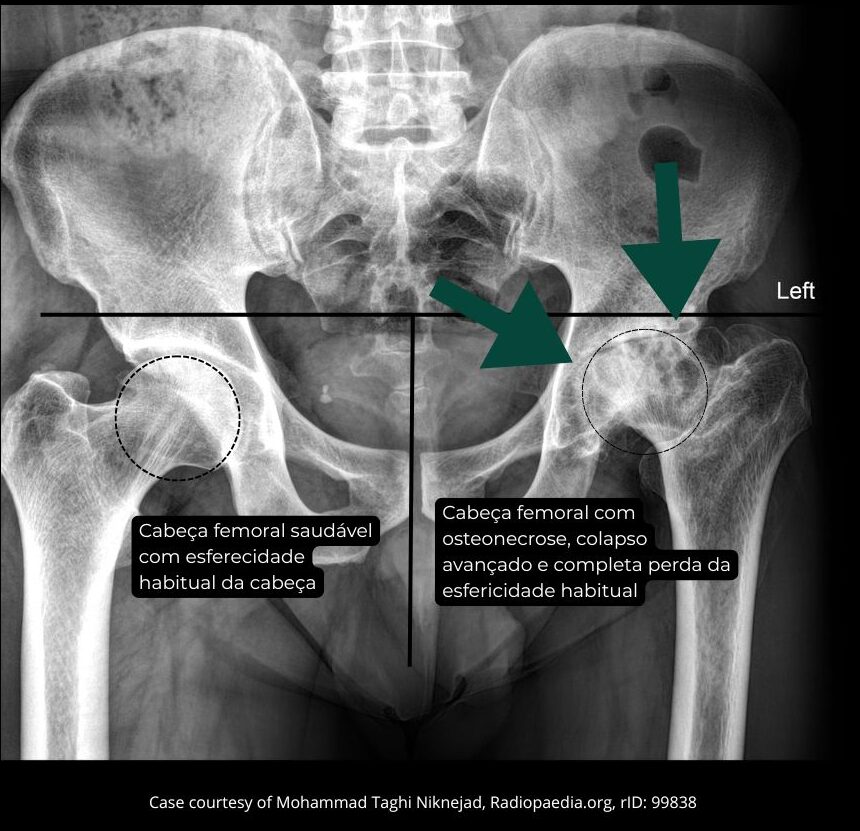

Na fase avançada, ocorre perda da esfericidade da cabeça do fêmur, com deformação articular e desenvolvimento de artrose secundária do quadril.

A radiografia do quadril pode ser normal no início da doença, pois as alterações ocorrem inicialmente no interior do osso, tornando o exame pouco sensível para lesões precoces. Por esse motivo, um raio X sem alterações não exclui o diagnóstico.

A ressonância magnética do quadril é o exame de escolha e padrão-ouro para o diagnóstico da osteonecrose da cabeça do fêmur. Ela permite detectar a doença precocemente, avaliar a extensão da área acometida e identificar sinais de progressão, como edema da medula óssea, fratura subcondral, perda da esfericidade da cabeça do fêmur e afinamento da cartilagem, que indicam evolução para artrose secundária do quadril.